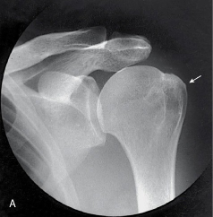

name the projection and rotational; label the part of the humerus the arrow is pointing to

AP external, greater tubercle